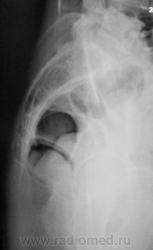

Из анамнеза известно, что примерно 2 месяца тому "летела" со сноутборга около 200 метров. Сейчас беспокоят боли в области спины, крестца и лонного сочленения. УЗИ было сделано всего, что только можно, везде - "норма". Хирурги, вроде-бы тоже ничего не находят. Но боли, видать значительные, походка вынужденная. На рентгенографию была направлена, как жест отчаяния, мол может быть, что-то найдут.

Рентгенограмма в прямой проекции.

1. Не исключаю поперечный перелом S5.

2. Лонное сочленение очевидно,подверглось значительному растяжению (имеется локальный вакуум-феномен слева), умеренно выраженые явления симфизита (опять же - постравматического).

Посттравматический симфизит - это такой медицинский диагноз есть? Тогда уж лучше - симфизопатияУлыбаюсь.  По поперечному перелому Л5 - тангенциальный эффект, сложение теней. По хорошему, надо бы доснять поясничный отдел позвоночника, в том числе в косых проекциях - на дугоотростчатые суставы, и грудо-поясничный переход.

1. По первым снимкам не отпускало впечатление о повреждении левого крестцово-подвздошного сочленения. После подготовки вроде-бы все нормально, но все равно что-то гложет.

2. А на боковой массе крестца справа разве не линия консолидирующегося перелома?